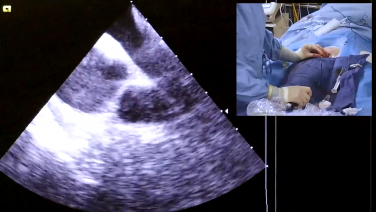

Intracardiac Echo Views During the AF Procedure with Brett Gidney, MD

Utilizing Intracardiac Echo During Transseptal Puncture with Brett Gidney, MD

Identifying Left Atrial Anatomy using Intracardiac Echo for Transseptal Puncture with James Brian Deville, MD

ICE Views for Atrial Flutter & Ventricular Structures with Andrew Brenyo, MD